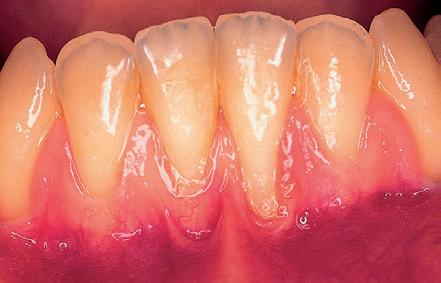

Mujer de 19 años remitida a nuestra consulta para tratar una dehiscencia de tejido blando que presentaba un implante localizado a nivel del 22 y que había sido colocado un año antes, debido a una agenesia. Esta paciente, había sido sometida durante su adolescencia a tratamiento ortodóntico. Los datos más relevantes de este caso son la presencia de un biotipo festoneado y fino y unas pequeñas retracciones en la encía marginal de 21 y 23 (pero no en el 22), así como

la existencia de dehiscencia ósea moderada en estos dientes. (Fig 13)

Para tratar la deshiscencia de tejido blando, se realizó un injerto de tejido conectivo submarginal asociado a un colgajo reposicionado (no desplazado) (Fig 14). En la g 15, se aprecia la cicatrización temprana con un buen sellado de la dehiscencia. La paciente

es remitida a su odontólogo de referencia y acude de nuevo a nuestra consulta nueve años más tarde. Lo curioso de lo ocurrido es que aunque el injerto fue ubicado en una posición submarginal, con los años sufre un cambio en su forma y volumen, desplazando a la encía en sentido coronal a nivel del 22 y cubriendo las pequeñas recesiones existentes en 21 y 23. (Fig 16) Lo llamativo de este caso es que el tejido blando ha cubierto parte de la corona del 22. Si bien guarda ciertas similitudes con el caso número 2, ya que ambos injertos tienen una ubicación

Fig 13: Año 1997. Mujer de 19 años que presenta una fenestración en el tejido blando, correspondiente a un implante colocado a nivel del 22. Se aprecia un biotipo extremadamente no y pequeñas recesiones en 21 y 23.

Fig 14: Se elevó un colgajo submarginal con dos incisiones liberadoras. El injerto de tejido conectivo, se ubicará sobre el lecho óseo y será cubierto por el colgajo. En ningún momento se involucra el margen gingival. Fig 15: Cicatrización temprana. La fenestración ha sido reparada.

Fig 16: Resultado a los 9 años. El injerto, ha sufrido un remodelado, con un cambio en su forma y volumen. Curiosamente, el margen gingival que se había respetado, se ha desplazado en sentido coronal sobre la corona del implante, cubriendo las pequeñas recesiones existentes en 21 y 23. Compárese con la Fig nº 13.

submarginal, se presenta una diferencia sustancial que merece la pena remarcar. En el caso número 2, existía una recesión y el tejido blando se había remodelado sobre la super cie radicular expuesta. En este último caso, sin embargo, no existía una recesión, habiendo crecido el tejido blando sobre la corona del implante, otorgándole una corona clínica más corta que la inicial.